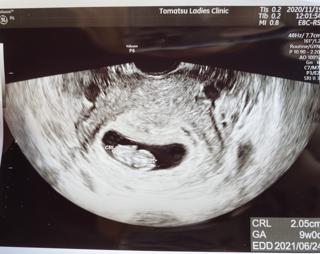

写真:9w0d:み―ちゃんさん

CRL23.2で大きさ的には9w2dだけど、最終生理日からの計算で9w0dに修正。

へその緒もしっかり見えて、小さな手足を動かしているのがすごく可愛かったです♡